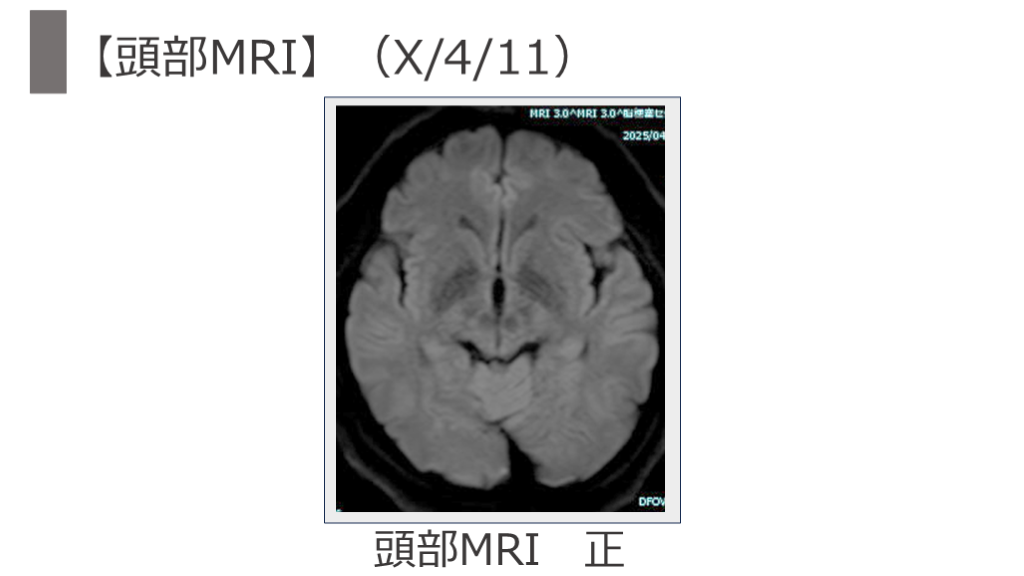

【頭部MRI】(X/4/11)   頭部MRI 正